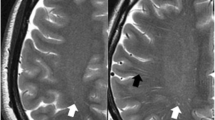

Subcortical gray matter volume

The comparisons of subcortical volume between groups are shown in Fig. 1. The Mann‒Whitney U test showed that compared with NCs, patients with MMD had significantly lower subcortical volumes in the bilateral thalamus, left caudate, bilateral putamen, bilateral hippocampus, bilateral amygdala, right pallidum, and right nucleus accumbens (FDR-corrected p value < 0.05).